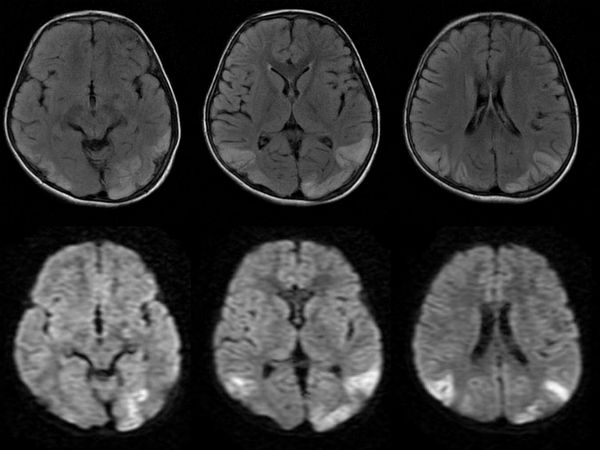

மூளை வீக்க நோய் பாதிப்பு குறித்து கண்டறியும் கருவிகள் கூட அங்குள்ள மருத்துவமனைகளில் இல்லாததால் பெரும்பாலானோர் இறக்க நேரிட்டுள்ளது.